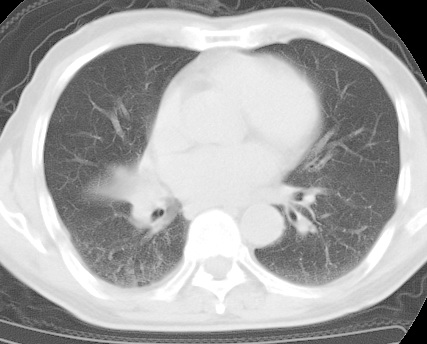

标题: CT24032:男65岁,咳嗽,吸烟20余年,无发热,咳痰 [打印本页]

标题: CT24032:男65岁,咳嗽,吸烟20余年,无发热,咳痰

考虑右肺中叶不张,请大家发表意见

右肺中叶不张、肺门轮廓增大,占位不除外;建议增强,必要时支气管镜详查。

右肺中叶支气管闭塞,中叶肺不张,右侧肺门见肿块影。中心型肺癌的可能大。建议支气管镜检查。

右中叶体积明显缩小,且其支气管未显示,先考虑:中心型肺癌班右中叶肺不张。

建议:支气管镜检查。

考虑右肺中叶中央型肺癌并右肺中叶肺不张;建议:行纤支镜检查。

右肺门旁类圆形肿块影,右肺中叶不张,建议纤支镜检查。

1右肺门旁类圆形肿块影,右肺中叶不张,建议纤支镜检查

2右侧胸膜增厚,右侧叶间胸膜区钙化

3右肺下叶小囊状透亮影考虑肺气肿

平片就可以诊断右肺中叶不张,做CT就是要找原因!中叶支气管开口不清,建议支气管镜检查。